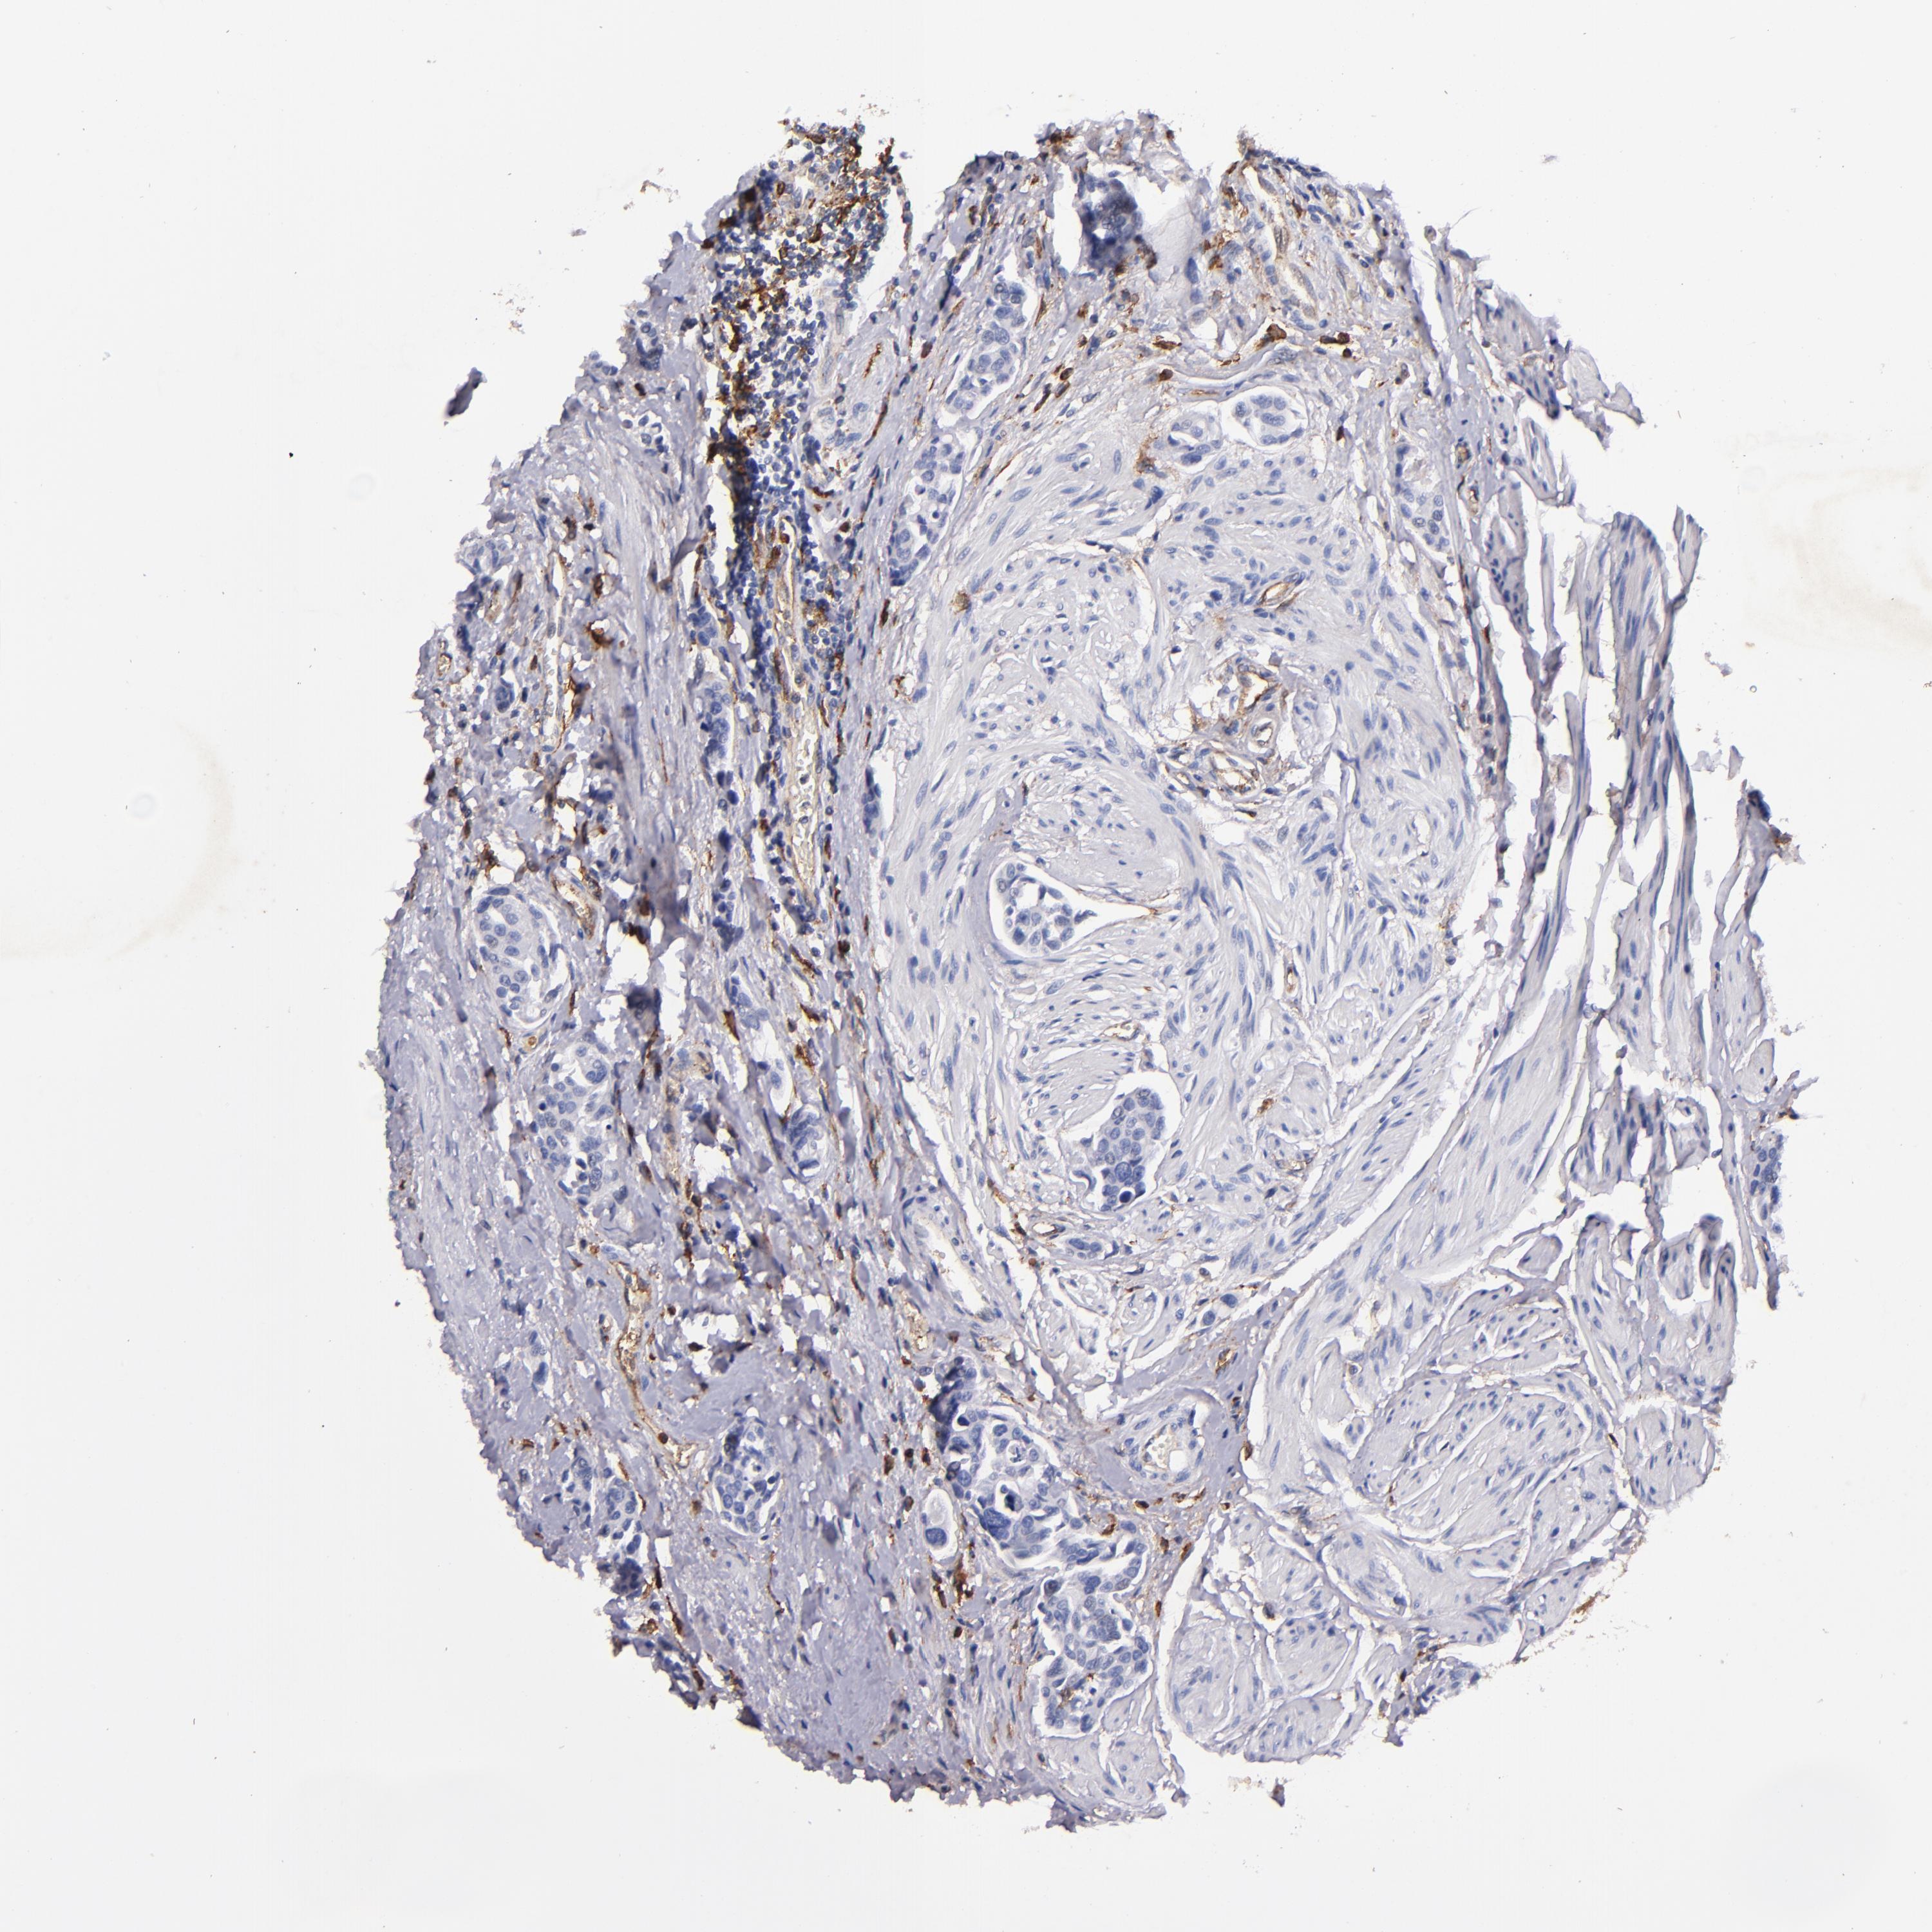

UROTHELIAL CANCER - Protein expressioni

A mouse-over function shows sample information and annotation data. Click on an image to view it in a full screen mode. Samples can be filtered based on level of antibody staining by selecting one or several of the following categories: high, medium, low and not detected. The assay and annotation is described here.

Note that samples used for immunohistochemistry by the Human Protein Atlas do not correspond to samples in the TCGA dataset.

Antibody stainingi

Antibody staining in the annotated cell types in the current human tissue is reported as not detected, low, medium, or high, based on conventional immunohistochemistry profiling in selected tissues. This score is based on the combination of the staining intensity and fraction of stained cells.

Each image is clickable and will lead to virtual microscopy that enables deeper exploration of all samples and also displays staining intensity scores, fraction scores and subcellular localization as well as patient and tissue information for each sample.

Antibody HPA054437

Antibody HPA058511

Antibody CAB002776

Antibody CAB015122

Staining

High

Medium

Low

Not detected

Intensity

Strong

Moderate

Weak

Negative

Quantity

>75%

75%-25%

<25%

None

Location

Nuclear

Cytoplasmic/membranous

Cytoplasmic/membranous,nuclear

Urothelial carcinoma, High grade

Urothelial carcinoma, Low grade

Urothelial carcinoma, NOS